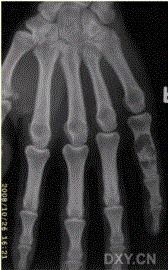

问题 患者男,28岁,偶尔发现右手第5近节指骨肿胀。查体:右手掌肿块,质硬,无明显压痛,无发热。进行了右手X线平片CT检查(下图)。 对于此病变影像学征象的描述,不正确的是

选项 A.右手小指骨干囊性膨胀性溶骨破坏 B.边缘清楚可见硬化缘 C.病灶内可见不规则钙化 D.可见骨膜反应 E.病变为偏心性生长

答案 E